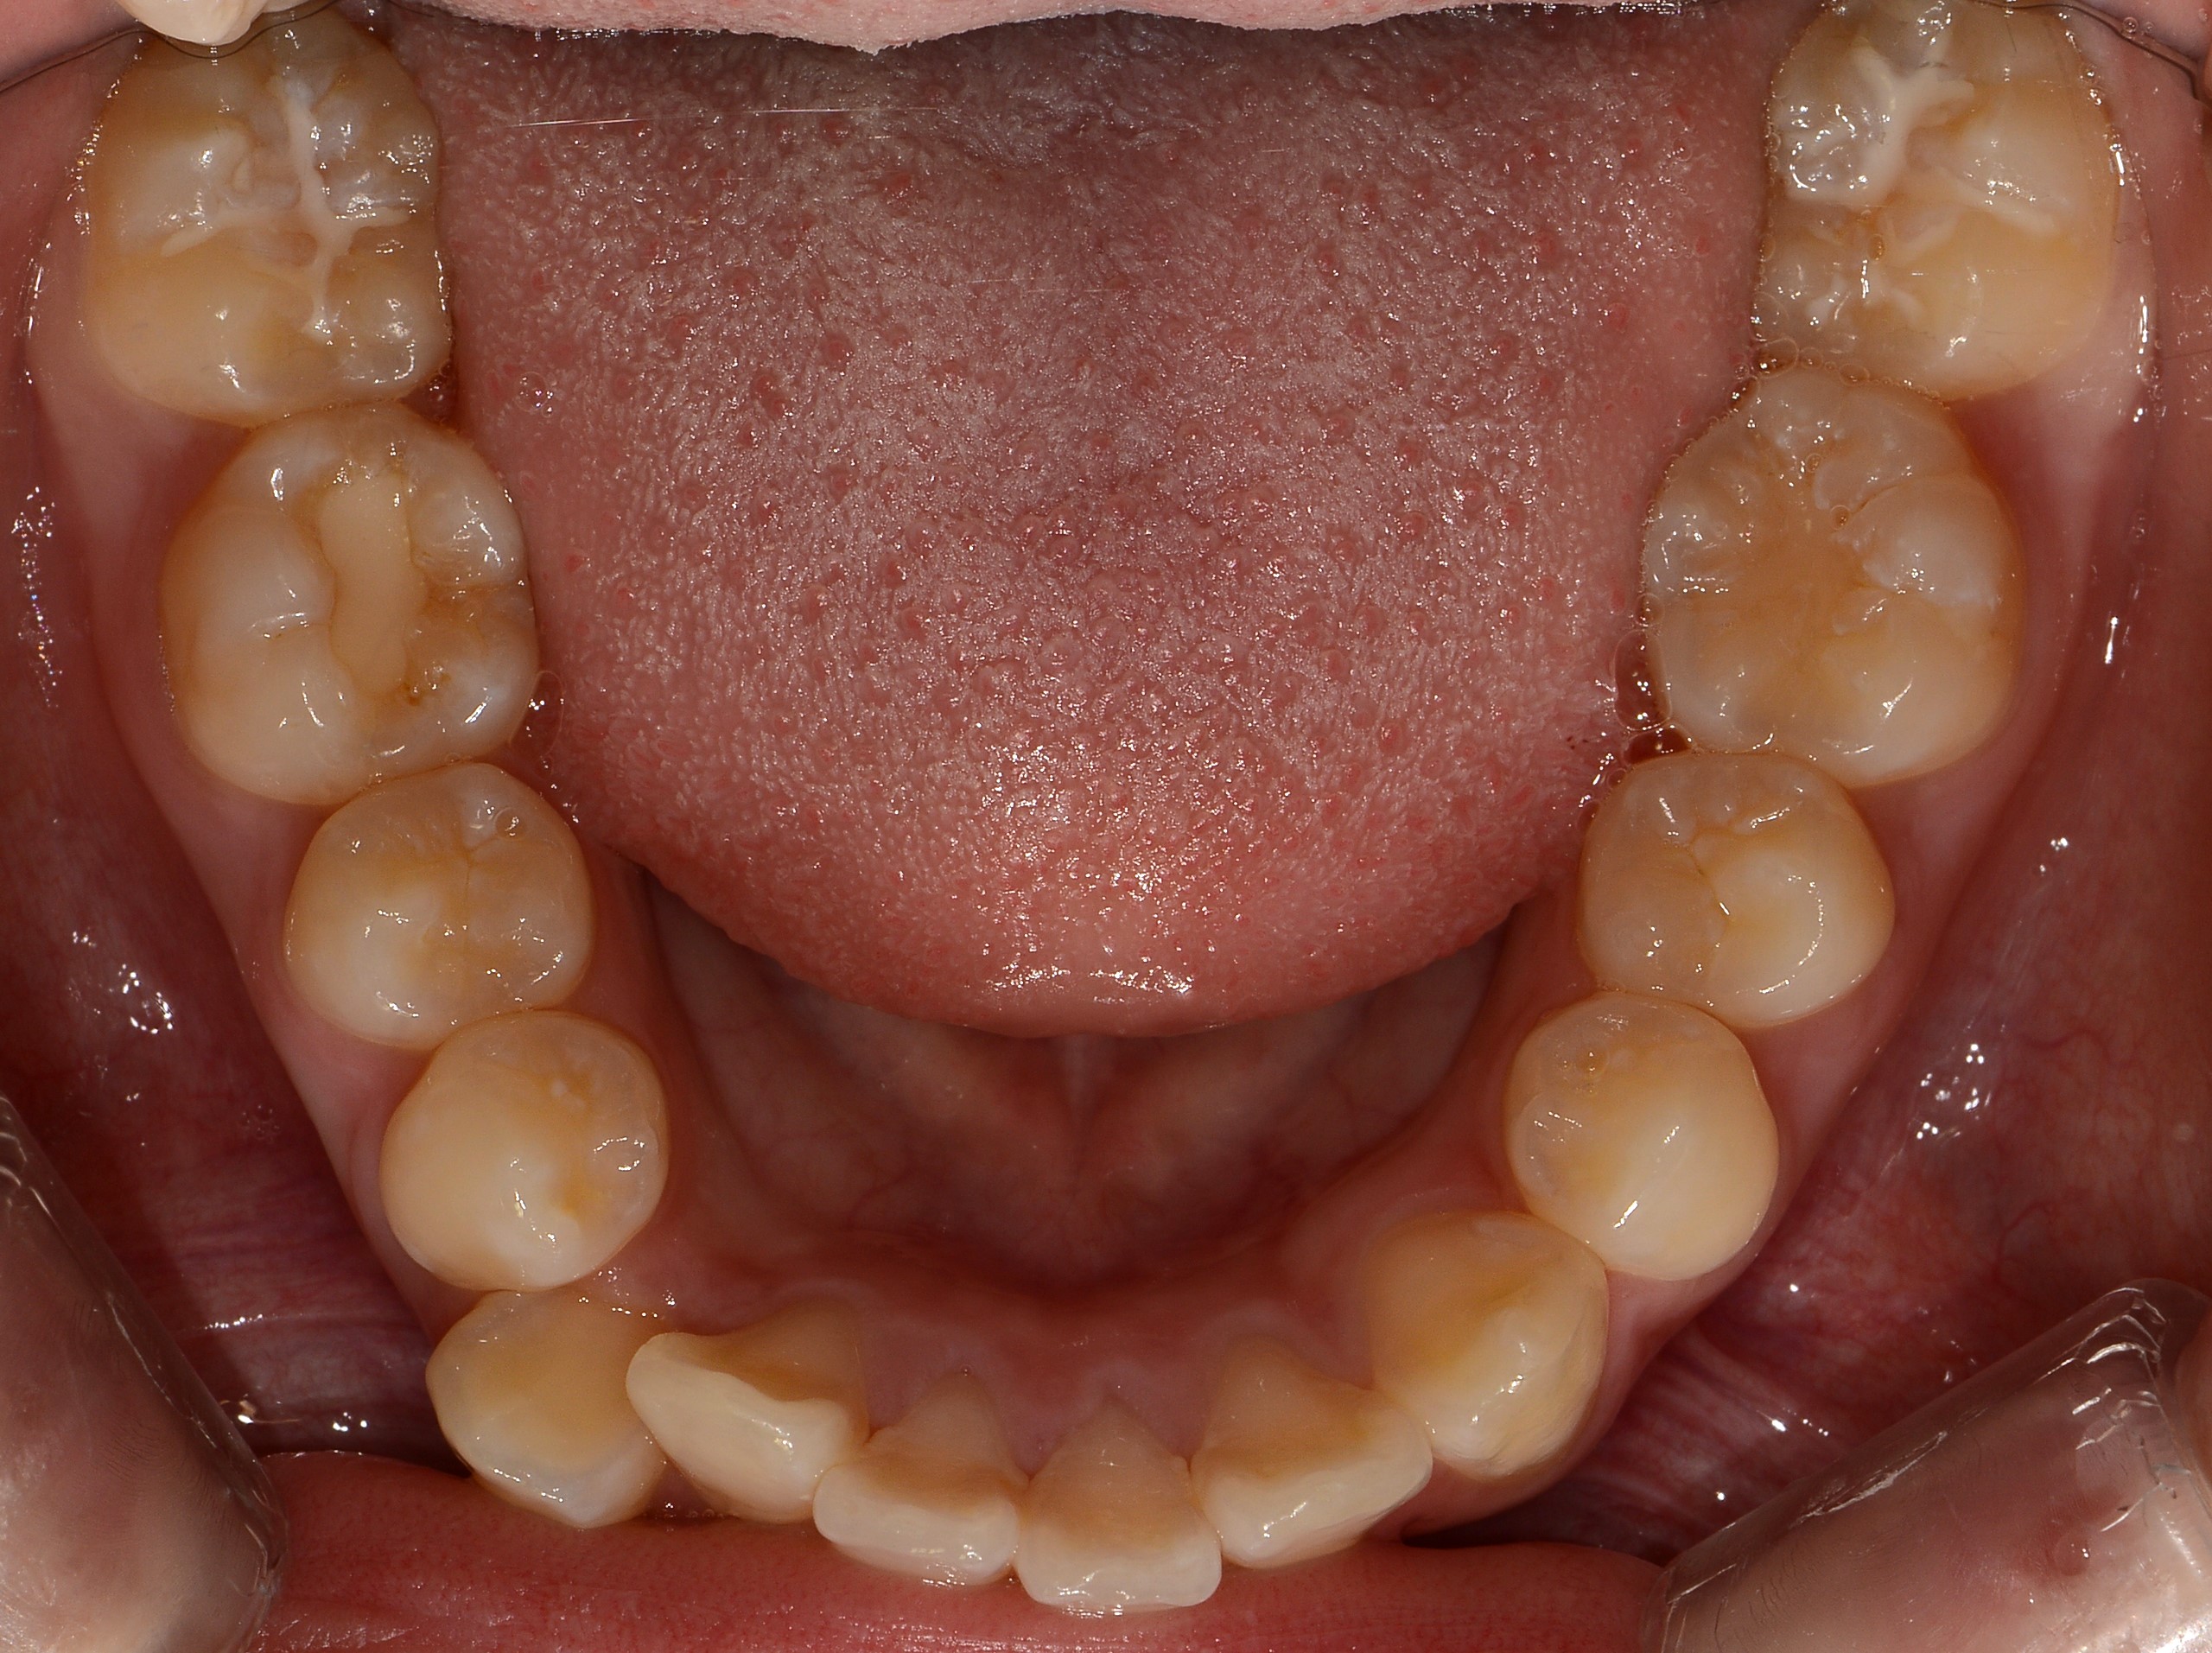

치료 전 사진입니다.